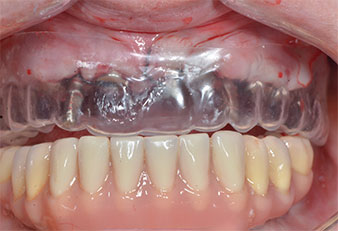

Three years later it was time for a maxillary denture of the same type. Based on CBCT planning sinus augmentation was avoided with the aid of short implants, and a surgical template was used to transfer the planned positions to the alveolar ridge (Figs. 1 and 2).

A flame-shaped, diamond-coated piezoelectric instrument (Piezomed I1) was used to mark the implant positions and to perform pilot preparation (Fig. 3). Care was taken to use an up and down movement, with reduced power, full irrigation and low pressure (below 300 g). Next a pilot instrument (Piezomed I2A/I2P) was applied for the initial 2 mm diameter enlargement of the implant sites (Fig. 4), followed by a 3 mm insert (Fig. 5).

Due to the relatively hard bone (D2) in this area, the 10 mm long implant sites at positions 11 and 21 were finalized with a 4 mm diameter rotary drill, in combination with a W&H WS-75 L surgical contra-angle handpiece, the W&H Implantmed implant motor and the optional W&H Osstell ISQ module. In contrast, due to the soft bone the posterior sites were prepared to a final 3 mm diameter using the Piezomed I3P instrument. The implants were finally placed transgingivally to osseointegrate for three months (Figs. 6-10). The existing denture was retained on four provisional implants (Fig. 8).